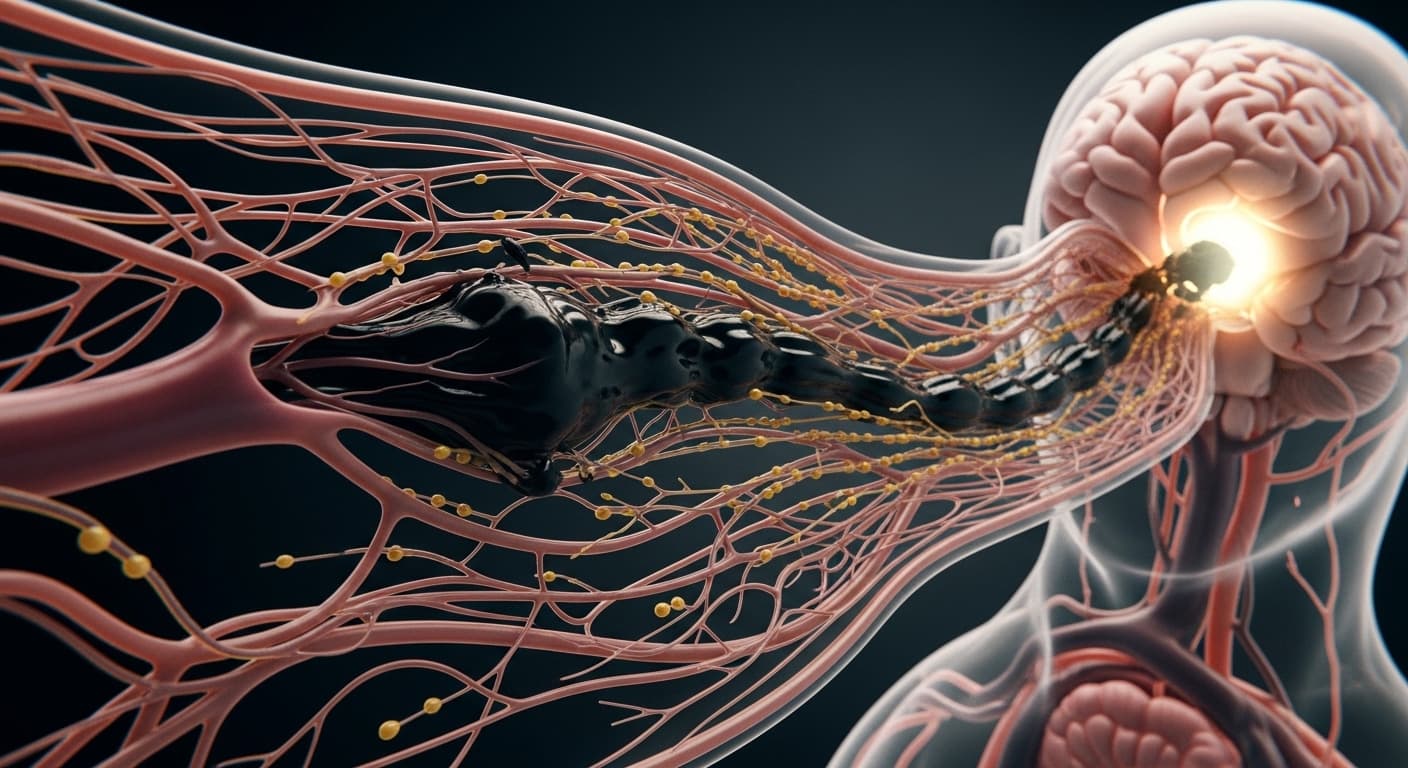

선조들의 지혜가 담긴 '담음' 개념은 현대 의학의 관점에서도 놀랍도록 설득력 있는 설명을 제공합니다. '뇌 안개' 증후군은 의학적으로 'Brain Fog'라고 불리며, 만성 염증, 장 건강 불균형, 미토콘드리아 기능 저하, 신경전달물질 불균형, 그리고 뇌 속의 노폐물 축적 등 복합적인 원인으로 발생한다고 보고 있어요. 이 모든 것들이 사실 '담음'이 하는 역할과 밀접하게 연결됩니다. 첫째, 만성 염증입니다. 몸속에 담음이 쌓인다는 것은 곧 만성적인 미세 염증 상태가 지속된다는 것과 유사합니다. 장 건강이 나빠지면 장 벽이 손상되어 '새는 장 증후군'이 발생하고, 미처 소화되지 않은 음식물 찌꺼기와 독소가 혈액을 타고 전신으로 퍼지면서 뇌를 포함한 장기에 염증 반응을 유발할 수 있습니다. 뇌 속의 미세아교세포(microglia)가 과도하게 활성화되어 뇌 염증을 일으키고, 이는 인지 기능 저하로 이어집니다. 둘째, 뇌 속의 노폐물 배출 시스템인 '글림프 시스템(Glymphatic system)'의 기능 저하입니다. 뇌는 잠자는 동안 척수액이 뇌 조직 사이로 흘러들어가 낮 동안 쌓인 노폐물(베타 아밀로이드 등)을 씻어내는 '뇌 세척' 과정을 거칩니다. 만약 수면 부족, 만성 스트레스, 혈액순환 장애 등으로 이 글림프 시스템이 원활하게 작동하지 않으면, 뇌 속에 노폐물이 쌓여 뇌 기능이 저하되고 '뇌 안개' 증상이 심해질 수 있습니다. 동의보감에서 말하는 '담음이 머리의 맑은 기운을 막는다'는 표현은 뇌 속 노폐물 축적이라는 현대적 해석과 일맥상통합니다. 셋째, 대사 기능 이상입니다. 혈당 스파이크가 반복되거나 인슐린 저항성이 생기면 뇌는 필요한 포도당을 제대로 활용하지 못하고, 이는 곧 뇌 세포의 에너지 부족으로 이어집니다. 에너지가 부족한 뇌는 집중력과 기억력을 제대로 발휘하기 어렵고, 이 또한 '담음'처럼 몸속 대사 흐름이 탁해진 결과로 볼 수 있습니다. 또한 갑상선 기능 저하, 부신 피로 등 내분비 기능의 불균형도 뇌 안개를 유발하는 주요 원인으로 꼽히는데, 이 역시 몸의 조절 기능이 약해져 노폐물이 쌓이기 쉬운 상태를 의미합니다. 이처럼 멍하고 답답한 뇌 안개 증후군은 단순히 잠시 피곤한 상태가 아니라, 우리 몸 전반의 균형이 깨지고 노폐물이 쌓여 발생하는 복합적인 문제입니다. 담음의 관점에서 몸속 순환을 개선하고, 염증을 줄이며, 뇌 기능을 최적화하는 통합적인 접근이 필요해요.